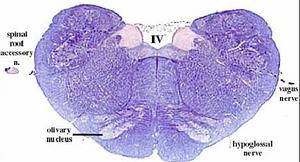

secciones transversales a diferentes niveles del tronco del encéfalo mostrando la localización de los núcleos neuronales aferentes de los nervios craneales

AFERENTES:

Somatoaferentes:

generales (GSA): boca y cara

-especiales (SSA): sentido de la visión y oído

Visceroaferentes:

- generales (GVA): recogen sensación de faringe y laringe

-especiales (SVA): sentido del gusto y del olfato